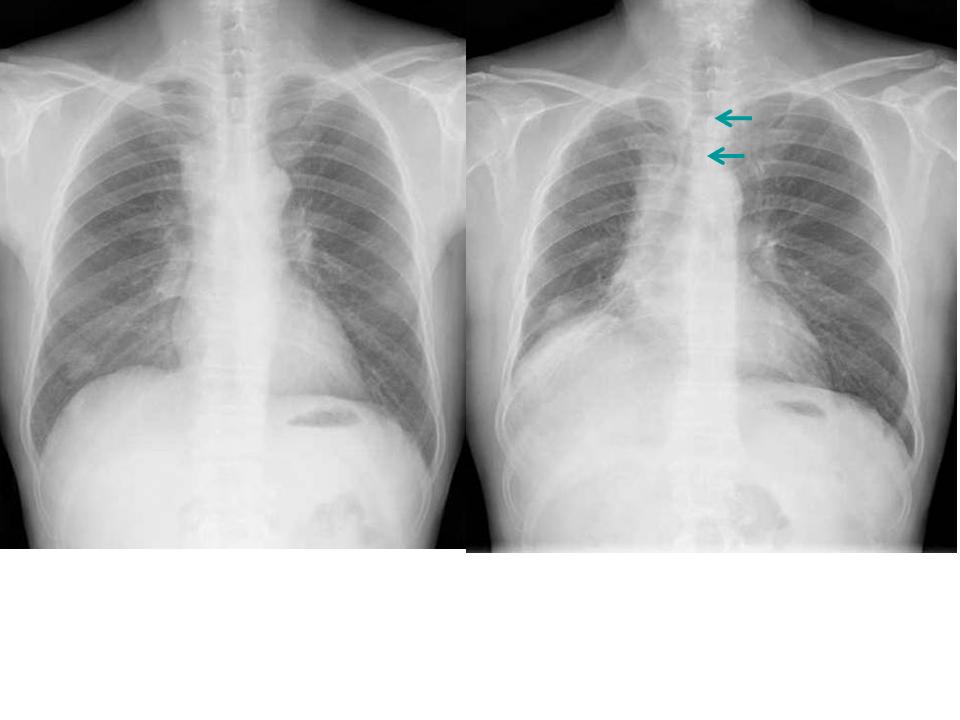

こちらを見て下さい。

わかりにくいかもしれませんが、このあたり。

気管が追いにくい、無くなっているようにも見えます。

気管狭窄ですね。こういう所見もレントゲンで捉えることができるのです。

レントゲンに含まれているたくさんの情報を、最大限利用したいものですね。